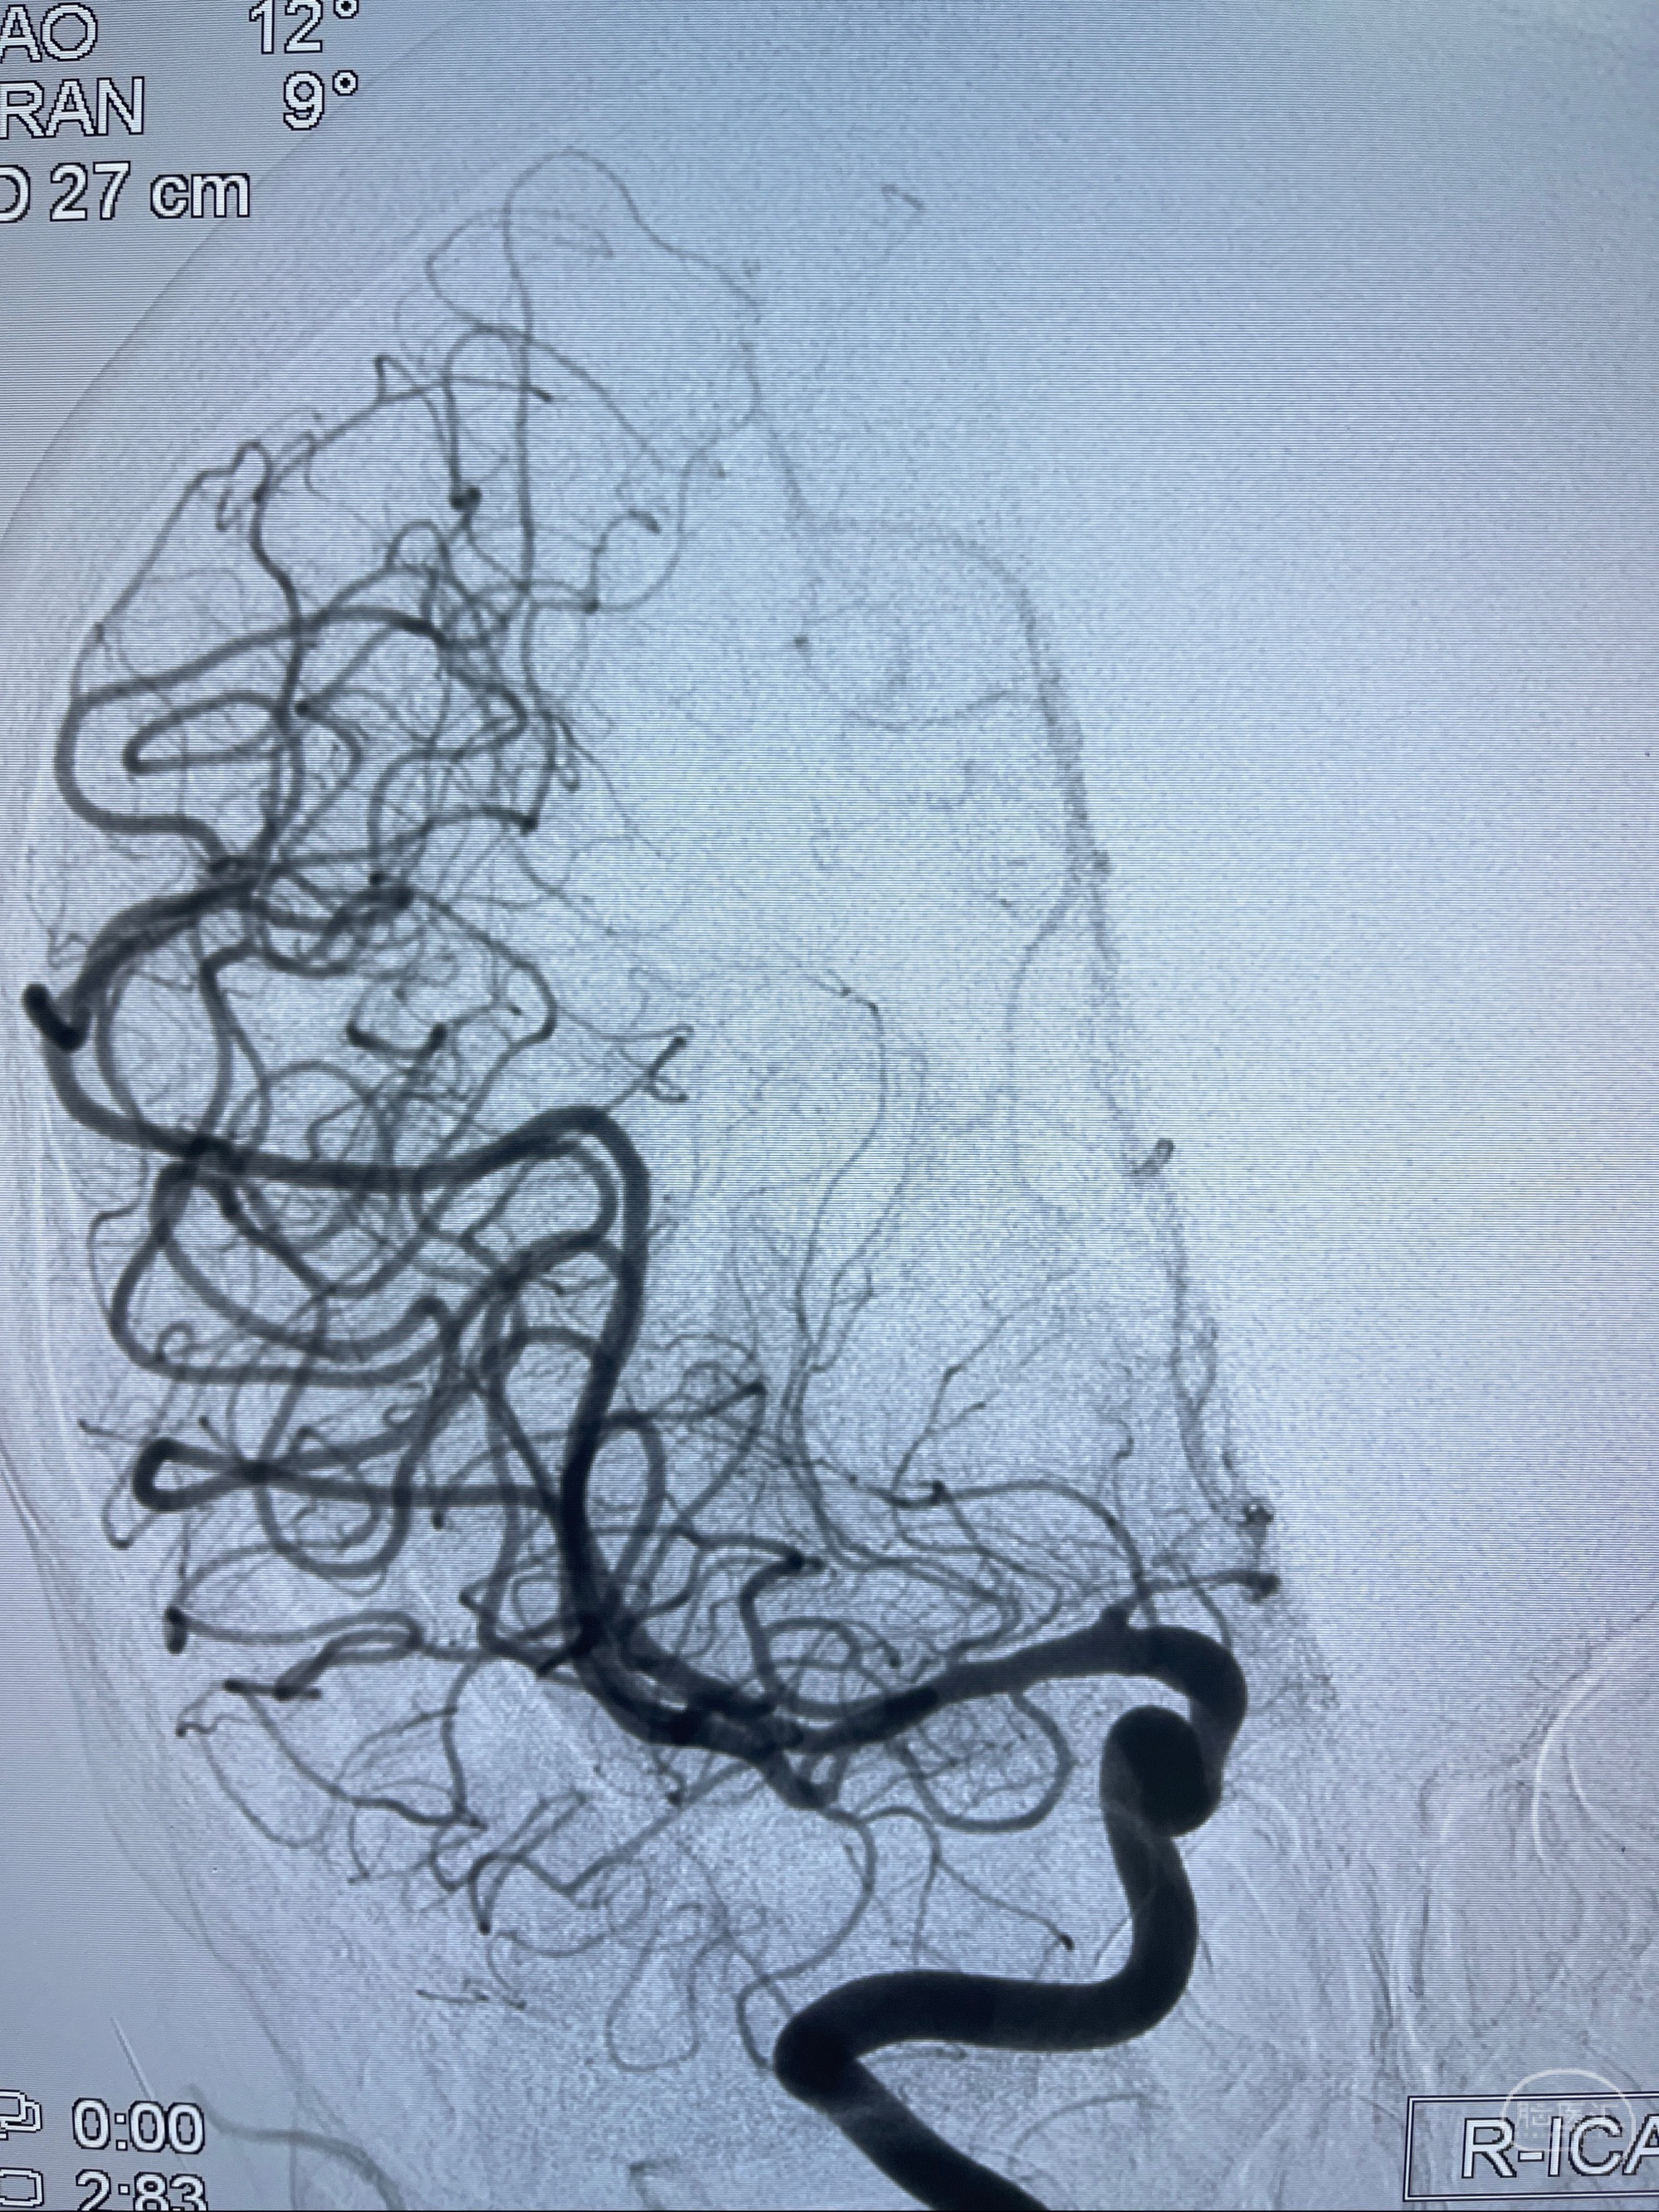

1.左侧大脑前动脉远侧段(A2-A5)动脉瘤

2023-08-23DSA:左侧前交通动脉瘤,左侧A3/4交界处多发动脉瘤